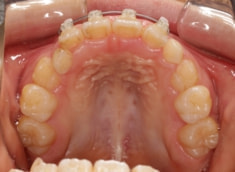

治療前

治療後(1年5ヶ月後)